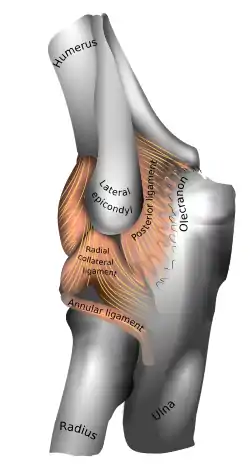

Capsule of elbow-joint (distended). Anterior aspect. | |

The annular ligament (orbicular ligament) is a strong band of fibers that encircles the head of the radius, and retains it in contact with the radial notch of the ulna.[1]

The annular ligament is attached by both its ends to the anterior and posterior margins of the radial notch of the ulna, together with which it forms the articular surface that surrounds the head and neck of the radius. The ligament is strong and well defined, yet its flexibility permits the slightly oval head of the radius to rotate freely during pronation and supination.[4][5]

The head of the radius is wider than the bone's neck, and, because the annular ligament embraces both, the radial head is "trapped" inside the ligament which thus acts to prevent distal displacement of the radius.[4] It helps to stabilise the proximal radial head,[6] and the radioulnar joint.[7]

Superiorly, the ligament is supported by attachments to the radial collateral ligament and the fibrous capsule of the elbow joint. Inferiorly, a few fibres attached to the neck of the radius support a fold of the synovial membrane without interfering with the movements at the joint.[4]